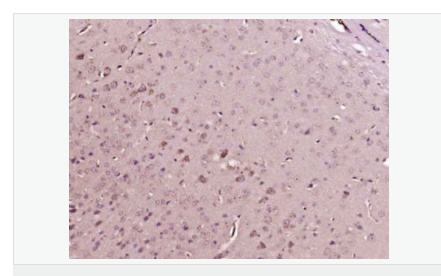

交叉反應(yīng):Human,Mouse,Rat(predicted:Phosphotyrosine) 推薦應(yīng)用:IHC-P,IHC-F,ICC,IF

| 產(chǎn)品應(yīng)用 | IHC-P=1:100-500 IHC-F=1:100-500 ICC=1:100-500 IF=1:100-500 (石蠟切片需做抗原修復(fù)) not yet tested in other applications. optimal dilutions/concentrations should be determined by the end user. |

| 細胞定位 | 細胞核 細胞漿 細胞膜 |

| 產(chǎn)品介紹 | The phosphorylation of specific tyrosine residues has been shown to be a primary mechanism of signal transduction during normal mitogenesis, cell cycle progression and oncogenic transformation, its role in other areas such as differentiation and gap junction communication, is a matter of active and ongoing research. Antibodies that specifically recognize phosphorylated tyrosine residues have proved to be invaluable to the study of tyrosine phosphorylated proteins and the biochemical pathways in which they function. SWISS: N/A CAS: 21820-51-9 Important Note: This product as supplied is intended for research use only, not for use in human, therapeutic or diagnostic applications. |